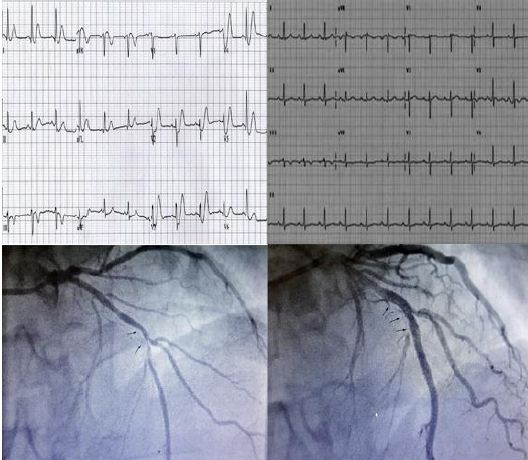

Paciente varón de 66 años de edad con antecedentes personales de diabetes mellitus tipo II, hipertensión arterial y obesidad, que acude al servicio de urgencias con dolor torácico. El dolor presentaba una evolución de 2 días, se desencadenaba con el ejercicio, y era descrito como una sensación de opresión central. El día que acude a urgencias presentó un episodio similar, pero desencadenado en reposo por la mañana, más intenso irradiando a ambos brazos y acompañado de náuseas. El paciente estaba libre de dolor a la llegada a urgencias. El ECG demostró ondas T bifásicas en V2 y V3 característica del síndrome de Wellens de tipo A (Figura 1). Los análisis de sangre mostraron niveles normales de troponina, después de una discusión con el cardiólogo el paciente fue llevado al laboratorio de hemodinámica y se observó una oclusión del 90-95% de la descendente anterior colocando un stent. El paciente tuvo una recuperación exitosa y fue dado de alta del hospital sin complicaciones.

Figura 1:ECG previo en ritmo sinusal, ECG a la llegada a urgencias con ondas T bifásicas en V2 y V3 característica del síndrome de Wellens de tipo A y coronariografía donde se observa lesión suboclusiva del 95% en el segmento medio de la descendente anterior así como normalización del ECG tras coronariografía.